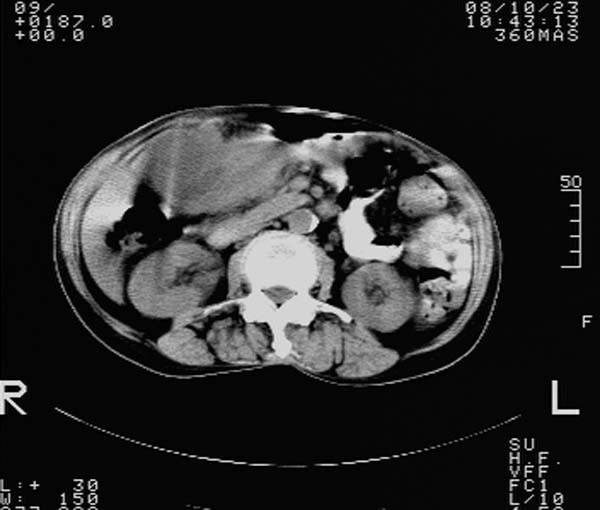

f,67y。反复右上腹痛。余无异常。

前五幅未服造影剂。后面图像有上传重复的。请战友们发表意见。

胆囊结石、胆囊癌伴邻近脏器受侵,不除外黄色肉芽肿性胆囊炎,建议增强扫描。肝多发囊性占位性病变,囊肿或囊性转移。

胆囊内结石,胆囊壁不规则增厚,胆囊胃窦区解剖结构欠清晰,楼主提示为少见病,考虑bouveret综合征?黄色肉芽肿性胆囊炎?肝内多发低密度占位,建议增强或b超